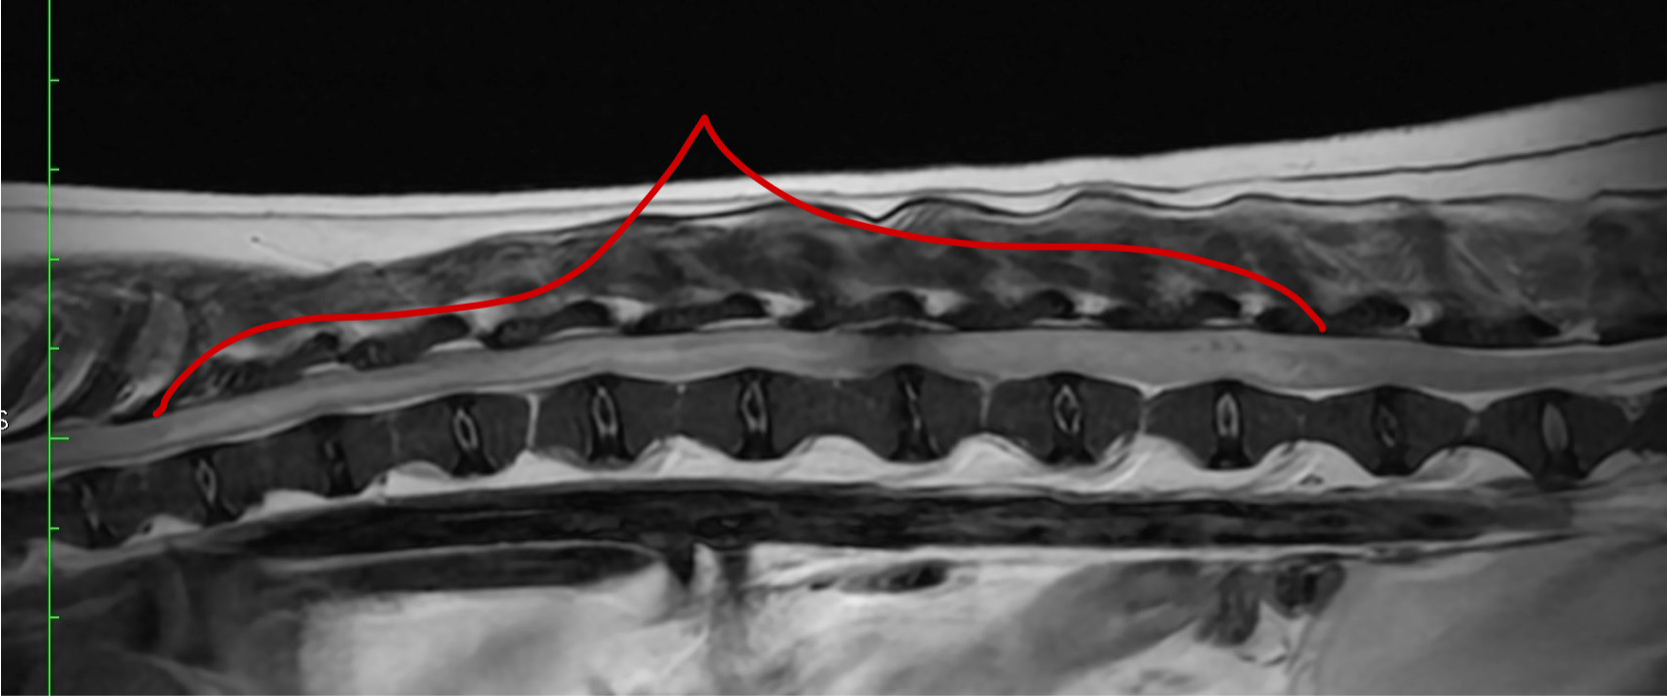

MRI画像 矢状断面

脊髄の広範囲の浮腫・脊髄軟化症を疑う所見